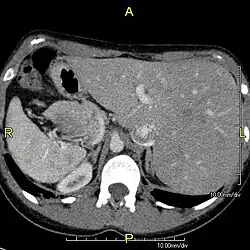

Zespół Kartagenera (ang. Kartagener’s syndrome) stanowi około połowy przypadków chorych z pierwotną dyskinezą rzęsek; w zespole tym, opisanym po raz pierwszy w 1904 roku, występuje klasyczna triada objawów, zwana triadą Kartagenera: zapalenie zatok przynosowych (sinusitis), rozstrzenie oskrzeli (bronchiectases) i odwrócenie trzewi (situs inversus). Postuluje się wpływ nieprawidłowej funkcji rzęsek w patogenezie zaburzenia embriogenezy, jakim jest situs inversus. Nazwa zespół nieruchomych rzęsek stosowana wcześniej wymiennie z terminem pierwotnej dyskinezy rzęsek nie powinna być używana, ponieważ nieprawidłowo zbudowane rzęski posiadają zdolność do ruchu; nie wystarcza ona jednak aby nabłonek urzęsiony mógł prawidłowo pełnić swoją funkcję.

- klasyczna triada: zapalenie zatok, rozstrzenia oskrzeli i situs inversus występuje w około 50% przypadków i stanowi podstawę rozpoznania zespołu Kartagenera